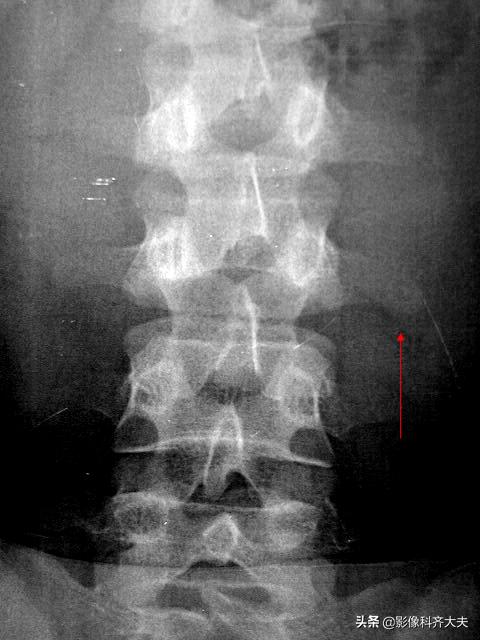

椎体压缩骨折常合并上下关节突、横突、椎弓根及棘突骨折,一般X线平片正侧位可观察清楚。

上下关节突间的椎板,称为椎弓峡部,此处骨折常发生在腰4或腰5,因身体重力向前分力作用,可使椎体向前滑脱。椎弓峡部骨折,以脊柱斜位X线片显示清楚。

腰3左侧横突中段可见纵行骨折线,骨折远端向下成角移位

腰椎正位示腰4上下关节突间斜行骨折线,腰椎侧位片示腰4前滑脱(Ⅱ度)